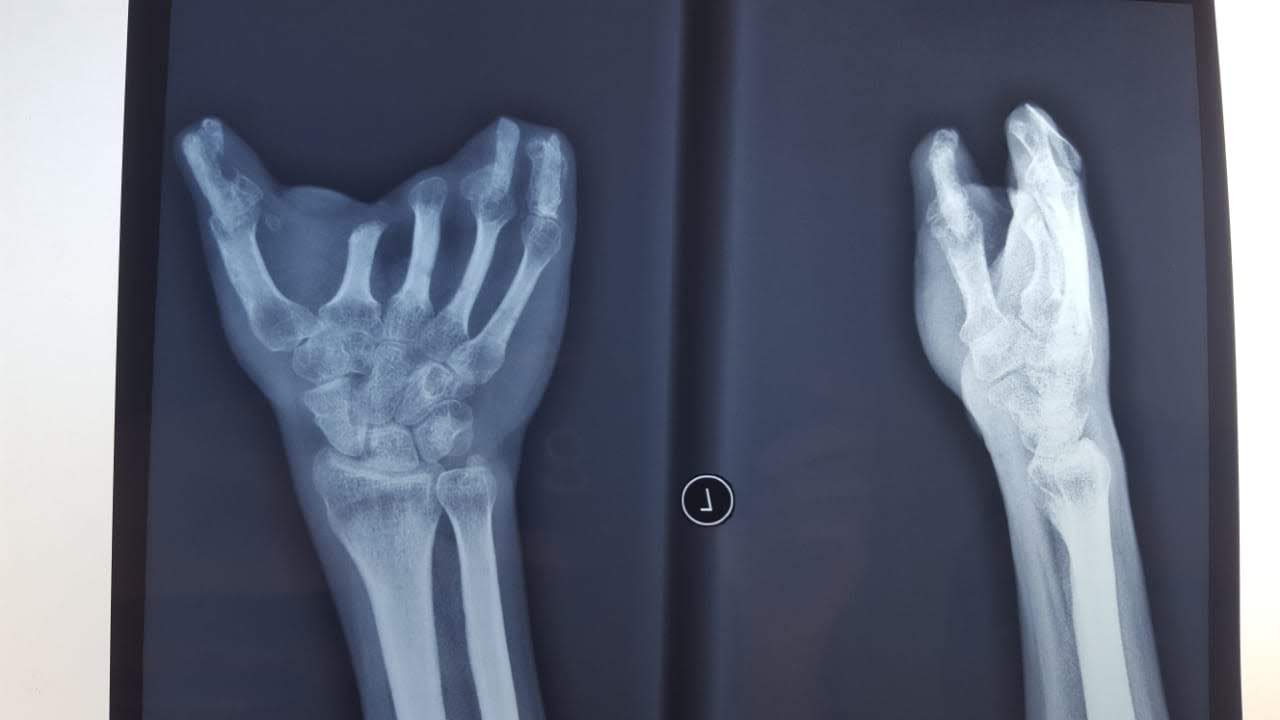

Manoplasty is distraction lengthening of fingers . Its is used for finger reconstruction . Causes of finger reconstruction are congenital, traumatic .

| well healed bone graft |

| healed bone graft |